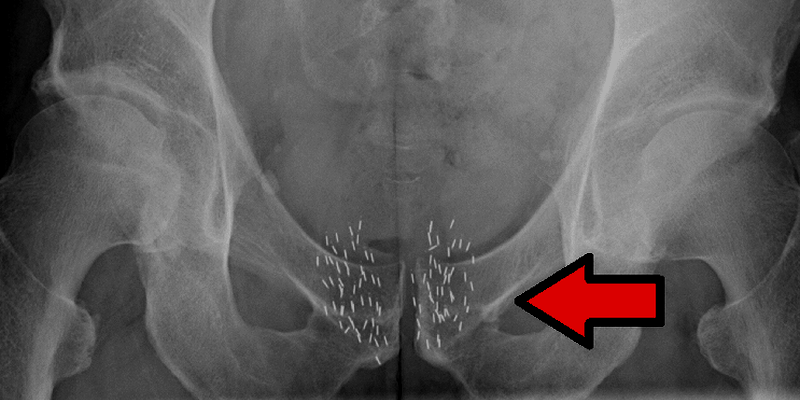

Radioterapi internal dilakukan dengan cara memasukkan sumber radiasi di dalam tubuh pasien. Sumber radiasi bisa berupa padat atau cair. Terapi radiasi internal dengan sumber padat disebut brachytherapy. Dalam jenis terapi ini, biji, pita, atau kapsul yang berisi sumber radiasi dimasukkan ke dalam tubuh, di dalam atau di dekat tumor.

Seperti radioterapi eksternal, brachytherapy adalah jenis pengobatan lokal yang hanya menargetkan satu bagian spesifik pada tubuh paisen. Dengan brachytherapy, sumber radiasi dalam tubuh pasien akan mengeluarkan radiasi untuk sementara waktu.

Terapi radiasi eksternal digunakan dalam pengobatan banyak jenis kanker. Brachytherapy paling sering digunakan untuk mengobati kanker kepala dan leher, kanker payudara, kanker serviks, kanker prostat, dan kanker mata.